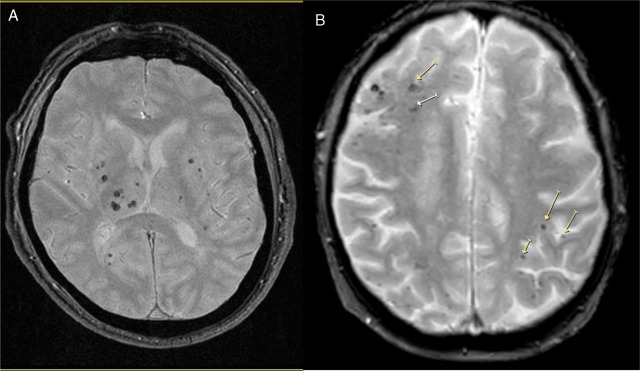

Enfermedad de los vasos cerebrales pequeños en la mediana edad y función cognitiva en etapas posteriores de la vida

20 enero 2025

La presencia de enfermedad de vasos cerebrales pequeños en la resonancia magnética de adultos asintomáticos se asoció de manera independiente con un deterioro del funcionamiento ejecutivo durante un período de seguimiento de 8 años en esta población general coreana de edad mediana a avanzada. The Lancet Regional Health Western Pacific, febrero de 2025.